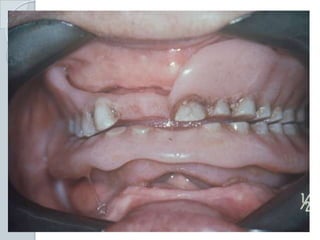

Trauma:Ill-Fitting dentures